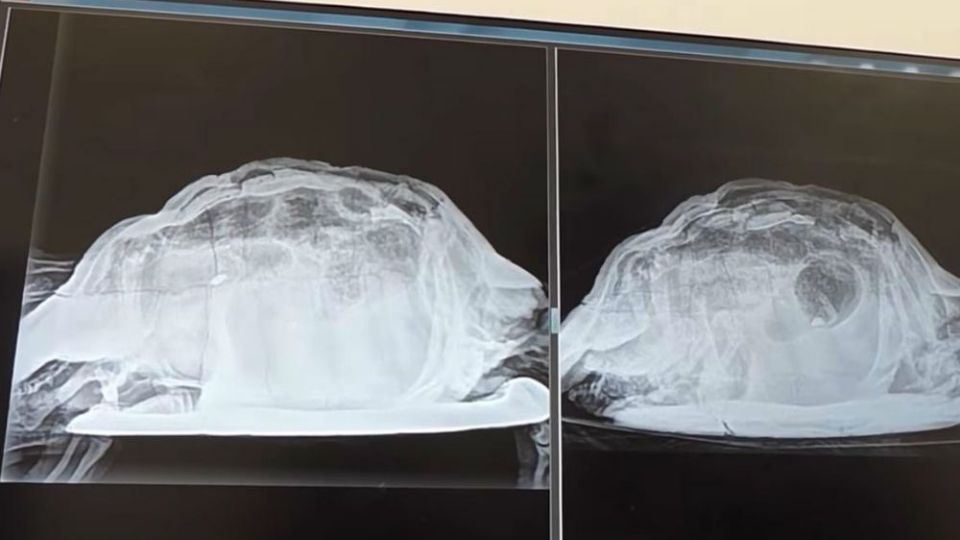

Encuentran tortuga en parte íntima de turista inglesa en Tenerife